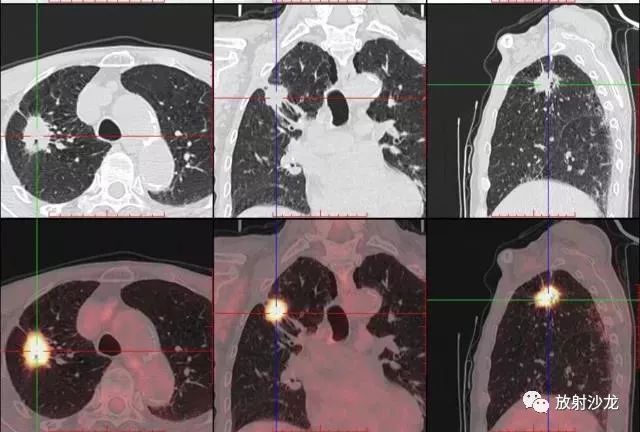

PET-CT等于PET+CT,包含PET(功能分子影像)與CT(解剖影像)的最優(yōu)化組合;即同時(shí)具有PET和CT的功能,但它絕不是二者功能的簡(jiǎn)單疊加,因?yàn)镻ET與CT優(yōu)勢(shì)互補(bǔ),“1+1>2”。PET-CT除了具備PET和CT各自的功能外,其獨(dú)有的融合圖像,將PET圖像與CT圖像融合, 可以同時(shí)反映病灶的代謝,可以早期診斷疾病的同時(shí),明顯提高診斷的準(zhǔn)確性。